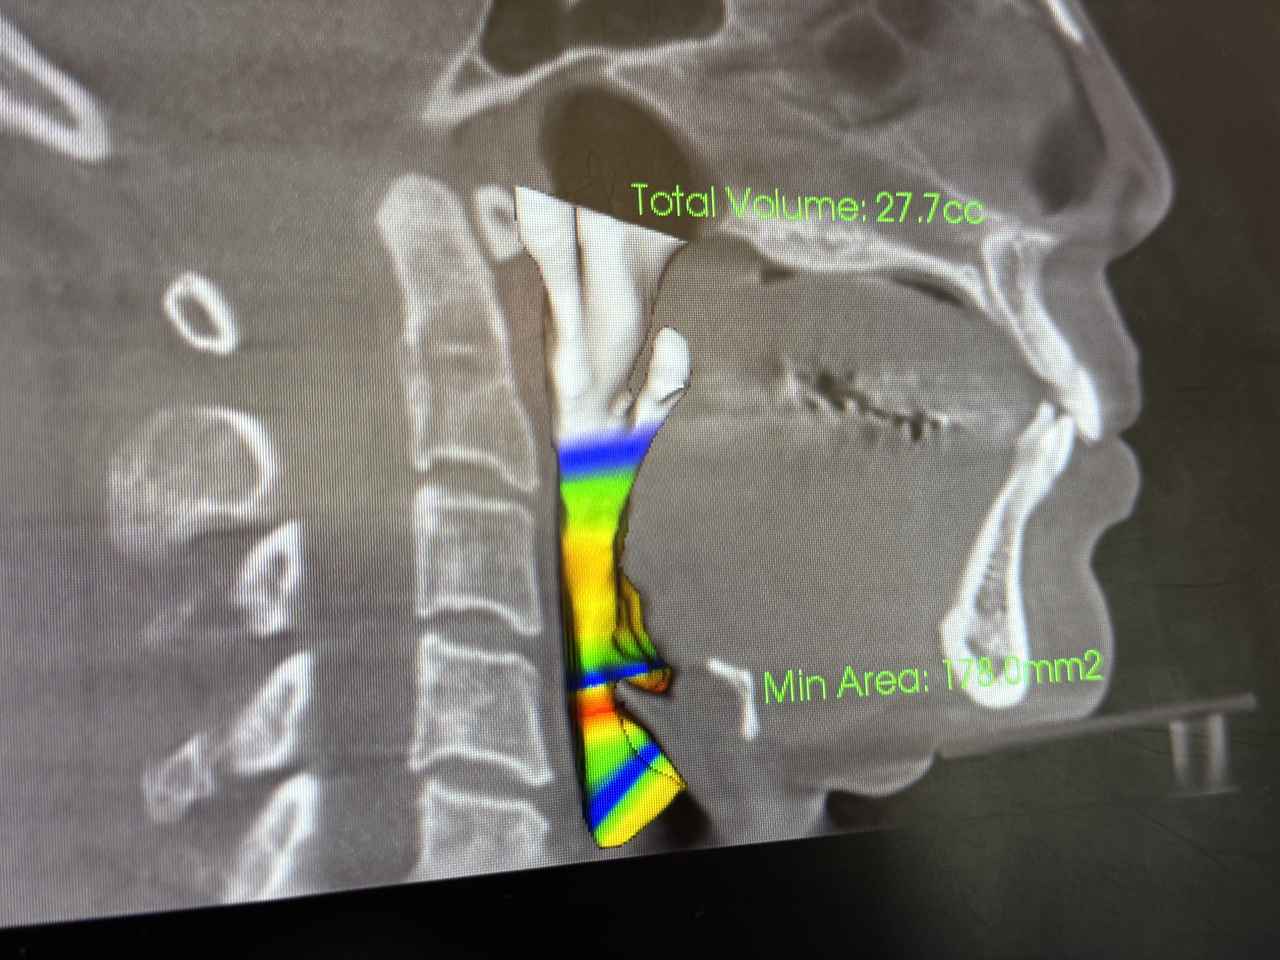

強い奥歯の噛みしめで頭蓋骨にまで影響がでていることが判明

気道が狭くなっているのまでわかります。

歯科用CTは、顎の骨や歯の位置を立体的に捉えることができるため、従来のレントゲンでは見えにくかった細部まで確認することができます。特に「こどもと女性の歯科クリニック」では、かみ合わせの診断に加えて、今回は、以下のような項目もチェックしてくれました。

呼吸の通り道(気道):

気道が狭くなっていると、口呼吸や睡眠の質に影響する可能性があります。

姿勢と口腔の関係は、想像以上に深い

姿勢が悪いと、顎が後方に下がり、かみ合わせがズレたり、気道が狭くなったりすることがあります。その結果、口呼吸になりやすくなったり、歯並びに影響が出たりすることも。歯科用CTは、こうした“見えない原因”を可視化することで、より根本的な治療や予防につなげることができます。歯のことだけでなく、姿勢や呼吸まで見てもらえるなんて驚きでした。